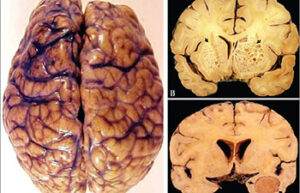

- Mice and rat brain edema test

- Mice and rat brain TTC test

- Evaluation of brain Evans blue staining test in rats and mice